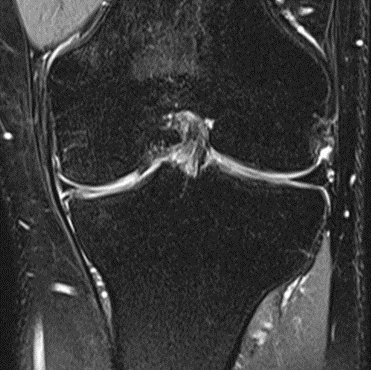

MRI scans illustrating the improvements regarding Group 2 are presented below, showing pre-treatment images with evident cartilage defects, pronounced bone marrow edema, and synovial inflammation, followed by post-treatment scans demonstrating improved joint structure, reduced edema, and decreased inflammation (Figures 12-29).

MRIs of Group 2

Figure 12: Female, 59 years, pre-intervention MRI.

Figure 13: Female of figure 12, 59 years, two-month follow-up MRI: MSC plus ChondroFiller® liquid.